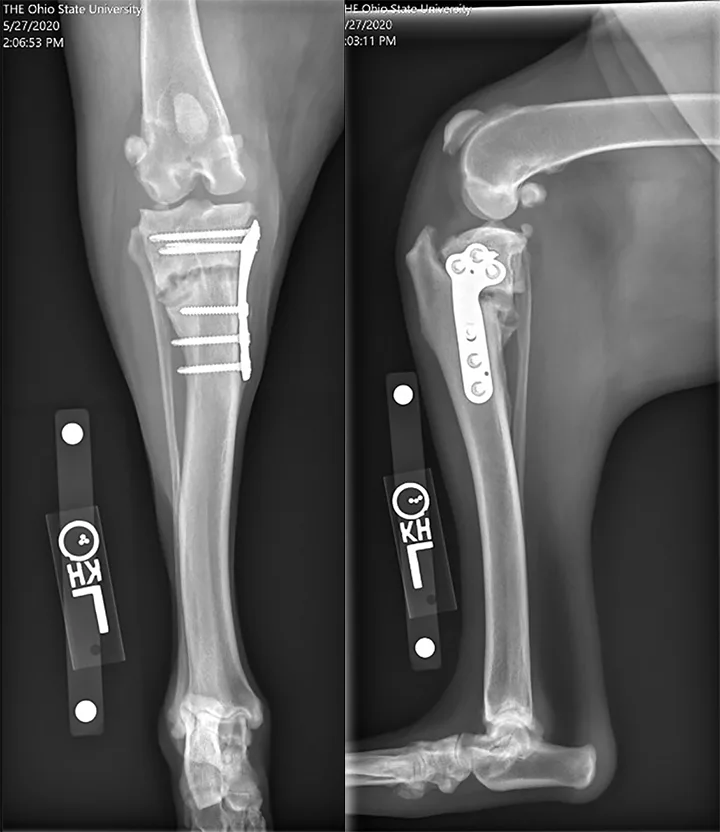

Immediate postoperative radiographs from a 2-year-old spayed medium-size crossbreed dog showing an inappropriately distally positioned TPLO. Distalizing the TPLO reduces the leveling achieved with planned rotation, leaves a narrow tibial crest (arrow), and positions the osteotomy in diaphyseal bone (slower to heal than metaphyseal bone). Also notable is the cranial position of the distal jig pin hole, which may predispose the patient to tibial diaphyseal fracture. This osteotomy position can be compared with that shown in Figure 4, in which the osteotomy position and resultant crest shape are appropriate.

The risk for tibial tuberosity fracture may be increased by an osteotomy position that results in a narrow crest (Figure 3), by bilateral simultaneous TPLO procedures, or by other factors that either decrease the strength of the patellar tendon’s anchor point or increase the pull of the patellar tendon.7,22 Many cases do not require intervention, although surgical stabilization may be required if the fragment is unstable.